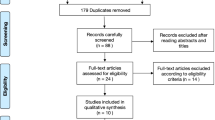

This study was a retrospective, case-control study of patients who underwent TKA surgery with either conventional instruments or the ABN (iAssist, Zimmer, Inc., Warsaw, IN) in The First Hospital of China Medical University. The inclusion criteria were as follows: (1) a diagnosis of primary tricompartmental osteoarthritis and (2) a history of unilateral TKA after conservative treatment failure. The exclusion criteria were as follows: (1) a knee-related operative or injury history, (2) a severe knee deformity (defined as a hip-knee-ankle (HKA) angle valgus > 30° or varus > 20°), (3) rheumatoid arthritis or another medical disease involving the knee, (4) haematological disorders, and (5) hip pathology that severely limited the range of motion. A total of 204 patients were enrolled in this study after applying the inclusion and exclusion criteria. From April 2016 to November 2017, 69 patients received a TKA using the iAssist to perform distal femoral and proximal tibial resection. During the same period, 135 patients received a TKA using conventional instruments. All procedures were performed by one experienced surgeon being familiar with the iAssist navigation system. This retrospective study was approved by the Ethics Committee of The First Hospital of China Medical University.

A total of 204 patients were selected and divided into two groups (CON: 135, ABN: 69) after applying the inclusion and exclusion criteria. Then, the ABN and CON groups were propensity score matched in a 1:1 ratio based on age, gender, BMI, HKA angel, KSS, and WOMAC score. After propensity-matched analysis, 82 patients (82 knees) were finally included in this study who underwent TKA using conventional instruments (n = 41) or the ABN system (n = 41). Clinical results before and after propensity matching are summarised in Table 1. No significant differences were found in gender, age, BMI, or the preoperative HKA, KSS, or WOMAC score between the two groups after matching.